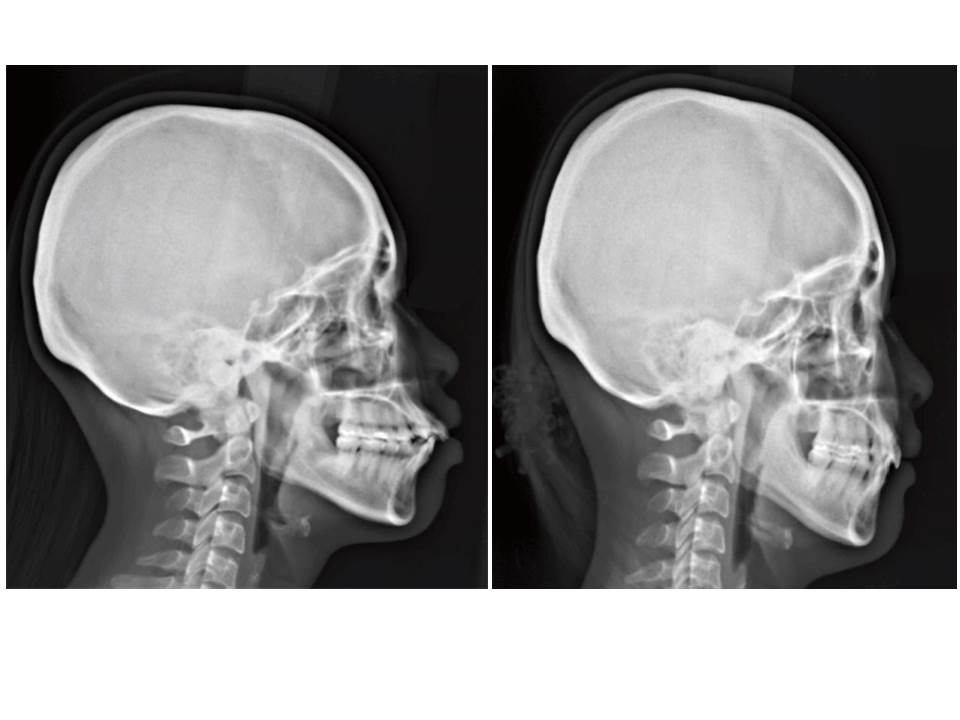

自鎖式矯正器不拔牙矯正

矯正訴求: ■ 咬合不正 ■ 牙齒凌亂